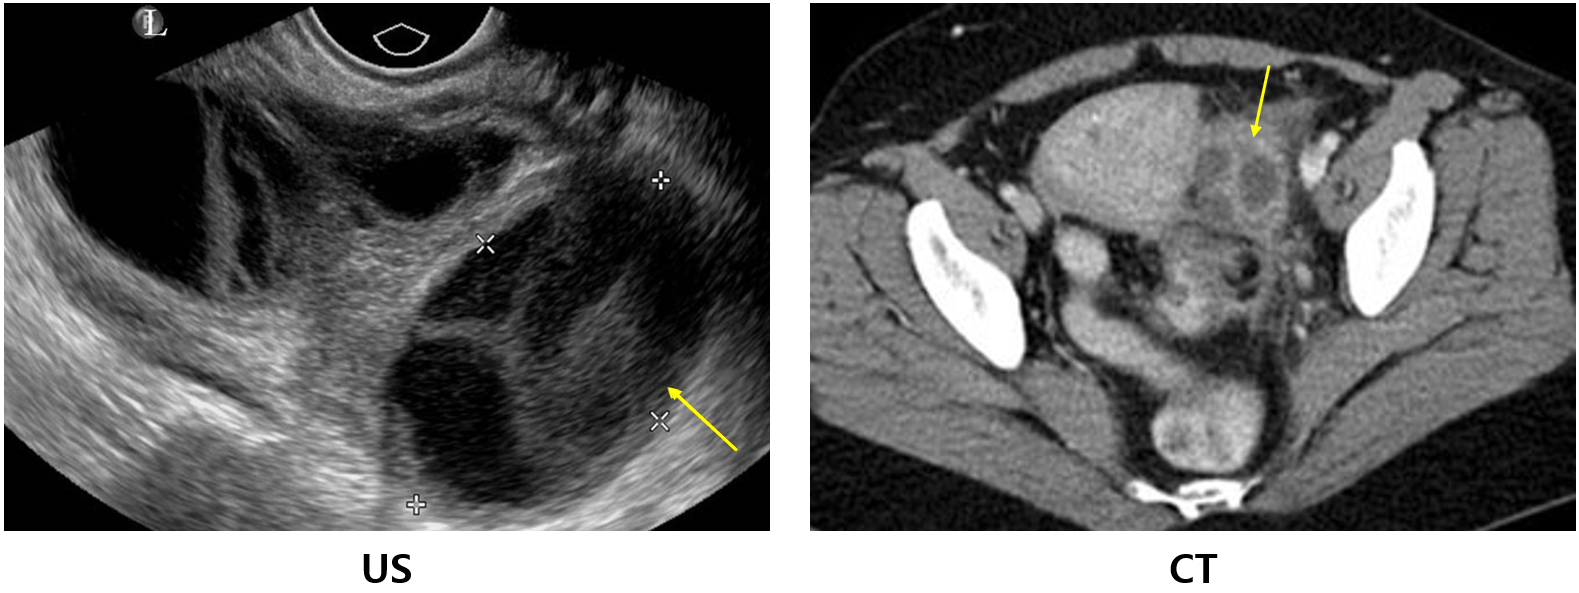

1) 난관난소농양(tubo-ovarian abscess, TOA, 난관난소고름집)

(1) 골반염이 진행되어 난관, 난소에 농양 형성

(2) 임상양상: 골반 덩이

(3) 검사소견: US/CT - multiloculated hypoechoic/hypoattenuating mass